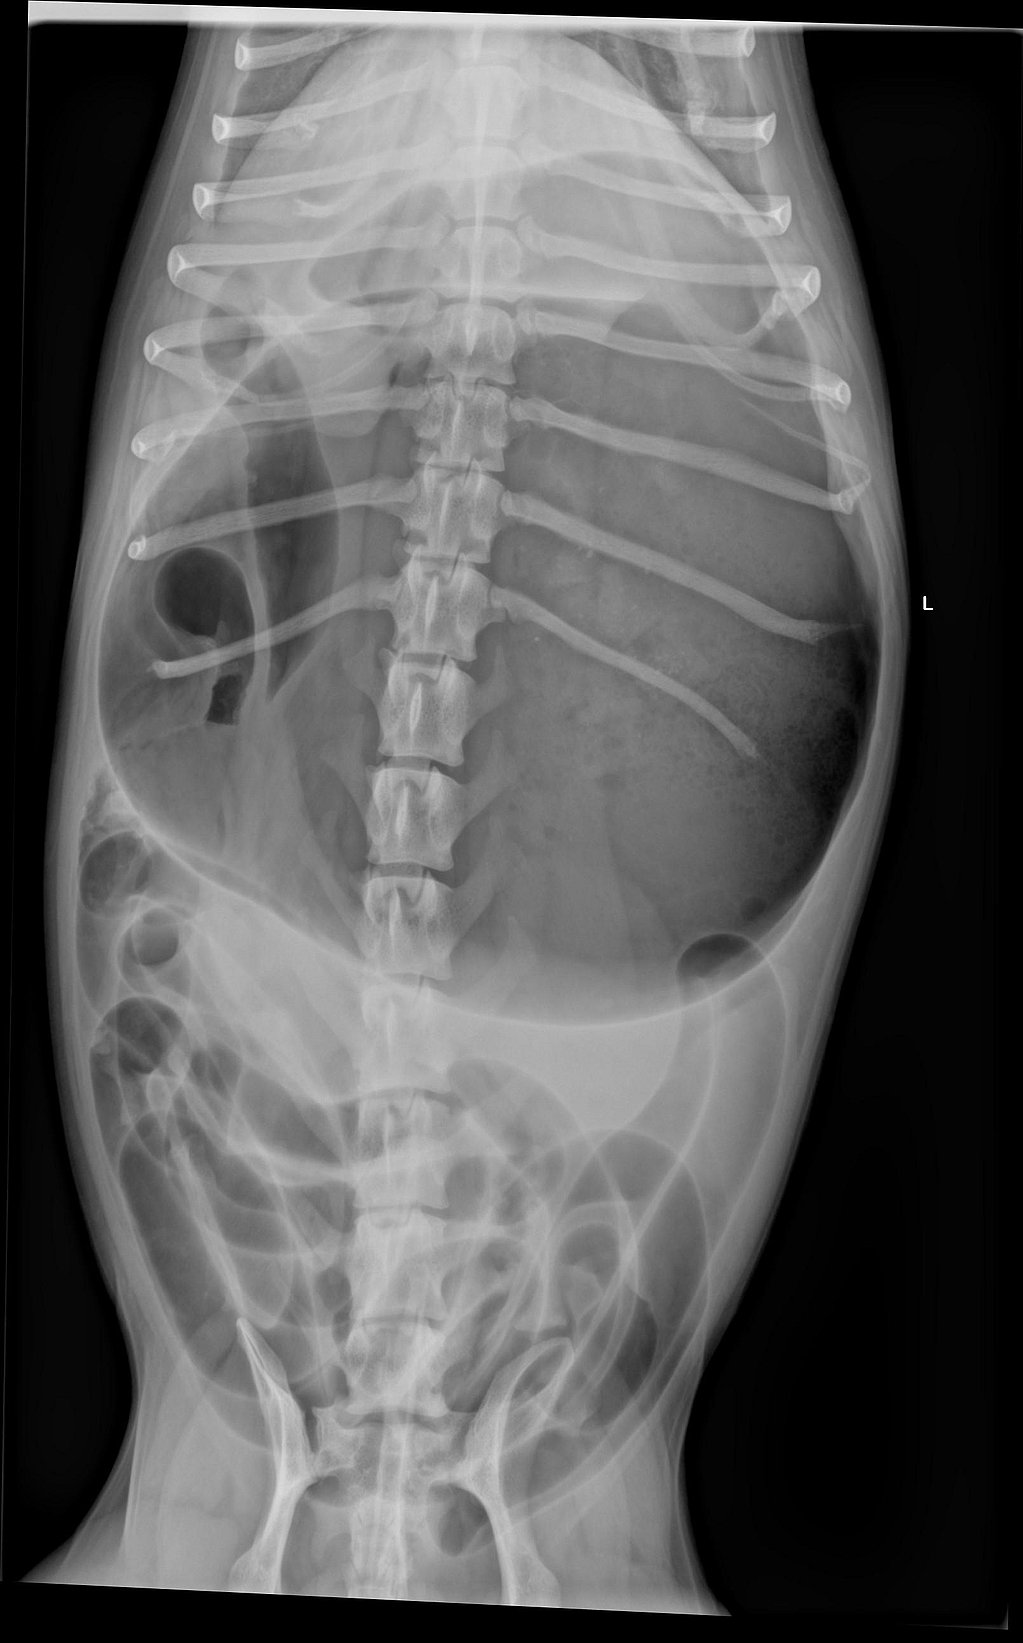

Hierna werden RX-foto’s genomen om het vermoeden van een maagkanteling te bevestigen. Bijgevoegde RX-foto’s in rechts laterale en ventrodorsale positie tonen een gedilateerde en gedraaide maag met de typische ‘double bubble’.